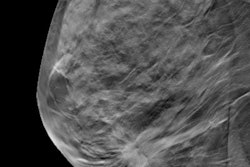

This week's top story was undoubtedly the turmoil within the antimammography-screening movement, as two of its most powerful figures left high-profile positions.

Dr. Peter Gøtzsche was ejected from the governing board of the Cochrane (formerly the Cochrane Collaboration), setting off a civil war between proponents of evidence-based medicine within the Cochrane organization and its individual centers. At almost the same time, Dr. H. Gilbert Welch resigned from Dartmouth College over allegations of plagiarism in a 2016 paper on overdiagnosis and breast screening. Our article on the developments was the top story of the week -- catch up by clicking here.

Supporters of breast screening can be excused if they are experiencing a bit of schadenfreude. Both Welch and Gøtzsche -- especially Gøtzsche -- have been thorns in their sides for years. Of the eight large randomized controlled trials on screening mammography, Gøtzsche excoriated the statistical methods used in the six that supported population-based breast screening, while upholding as gospel the two that found mammography to have no effect. He even wrote a book published in 2012, Mammography Screening: Truth, Lies and Controversy, that purported to expose breast screening as a "scandal of monstrous proportions."

While not as extreme, Welch consistently tried to poke holes in mammography's aura with a series of papers that focused on the alleged "harms" of breast screening, such as overdiagnosis and false positives. Welch's work alleged that nearly one-third of breast cancers detected by mammography screening were simply cases of overdiagnosis, and he and others proposed that the well-documented decline in breast cancer mortality was entirely due to better treatment, not screening.